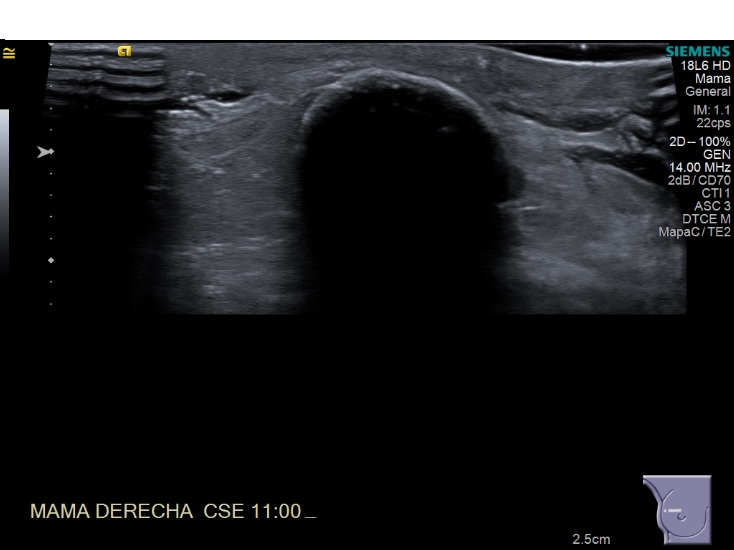

Crioablacion de tumor en mama derecha